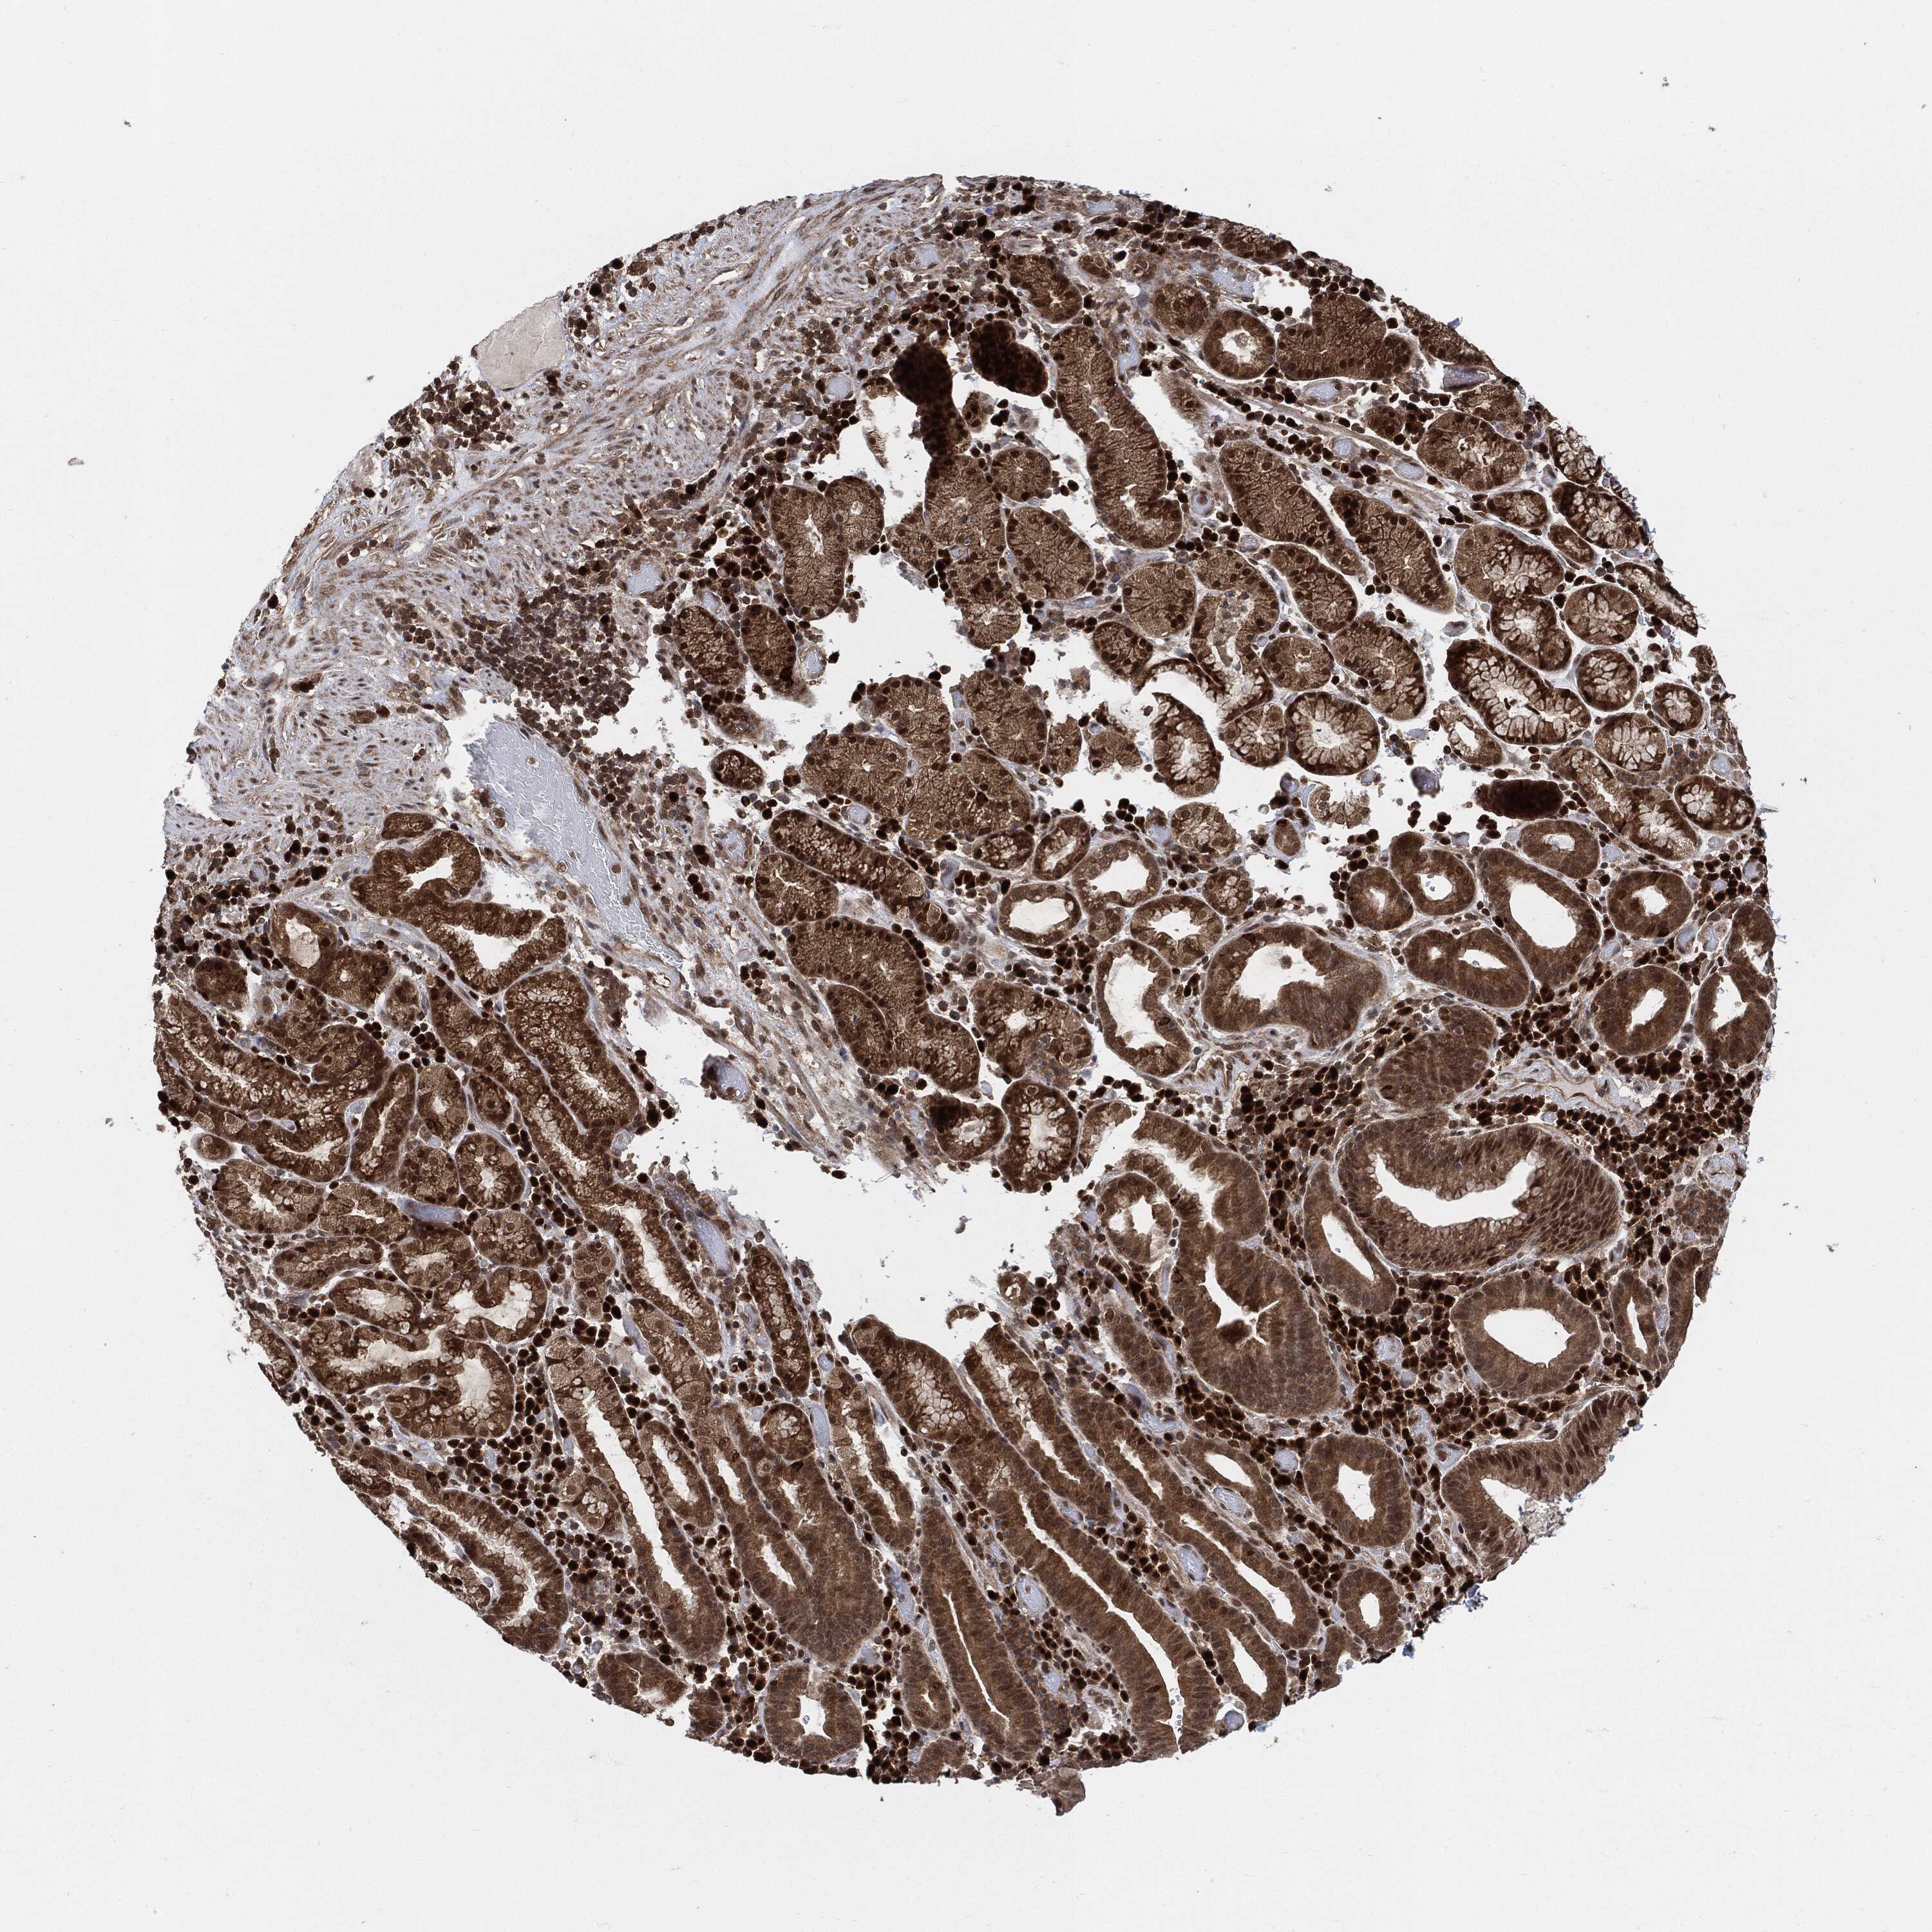

STOMACH CANCER - Protein expressioni

A mouse-over function shows sample information and annotation data. Click on an image to view it in a full screen mode. Samples can be filtered based on level of antibody staining by selecting one or several of the following categories: high, medium, low and not detected. The assay and annotation is described here.

Note that samples used for immunohistochemistry by the Human Protein Atlas do not correspond to samples in the TCGA dataset.

Antibody stainingi

Antibody staining in the annotated cell types in the current human tissue is reported as not detected, low, medium, or high, based on conventional immunohistochemistry profiling in selected tissues. This score is based on the combination of the staining intensity and fraction of stained cells.

Each image is clickable and will lead to virtual microscopy that enables deeper exploration of all samples and also displays staining intensity scores, fraction scores and subcellular localization as well as patient and tissue information for each sample.

Antibody HPA064369

Antibody HPA070199

Antibody CAB016787

Staining

High

Medium

Low

Not detected

Intensity

Strong

Moderate

Weak

Negative

Quantity

>75%

75%-25%

<25%

None

Location

Nuclear

Cytoplasmic/membranous

Cytoplasmic/membranous,nuclear

Adenocarcinoma, NOS

Adenocarcinoma, High grade